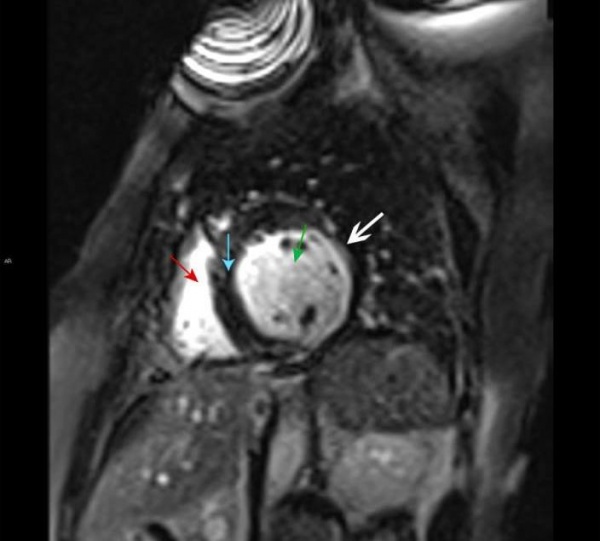

МРТ сердца. Правый желудочек (красная стрелка), левый желудочек (зеленая стрелка), желудочковая перегородка (синяя стрелка). Позднее усиление субэндокардиального контраста левого желудочка, характерное для инфаркта миокарда (белая стрелка).